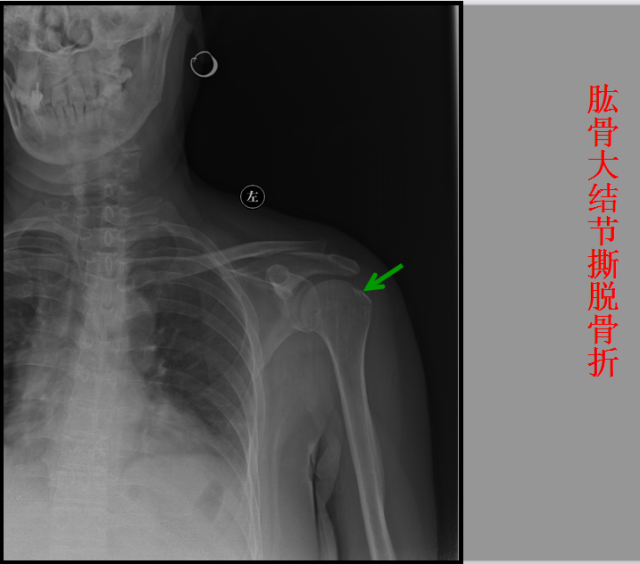

骨折篇

01

定义:骨折{Fracture}是指骨的完整性和连续性的折裂或粉碎。包括创伤性骨折、疲劳性骨折和病例理性骨折。 临床上以创伤性骨折*常见。